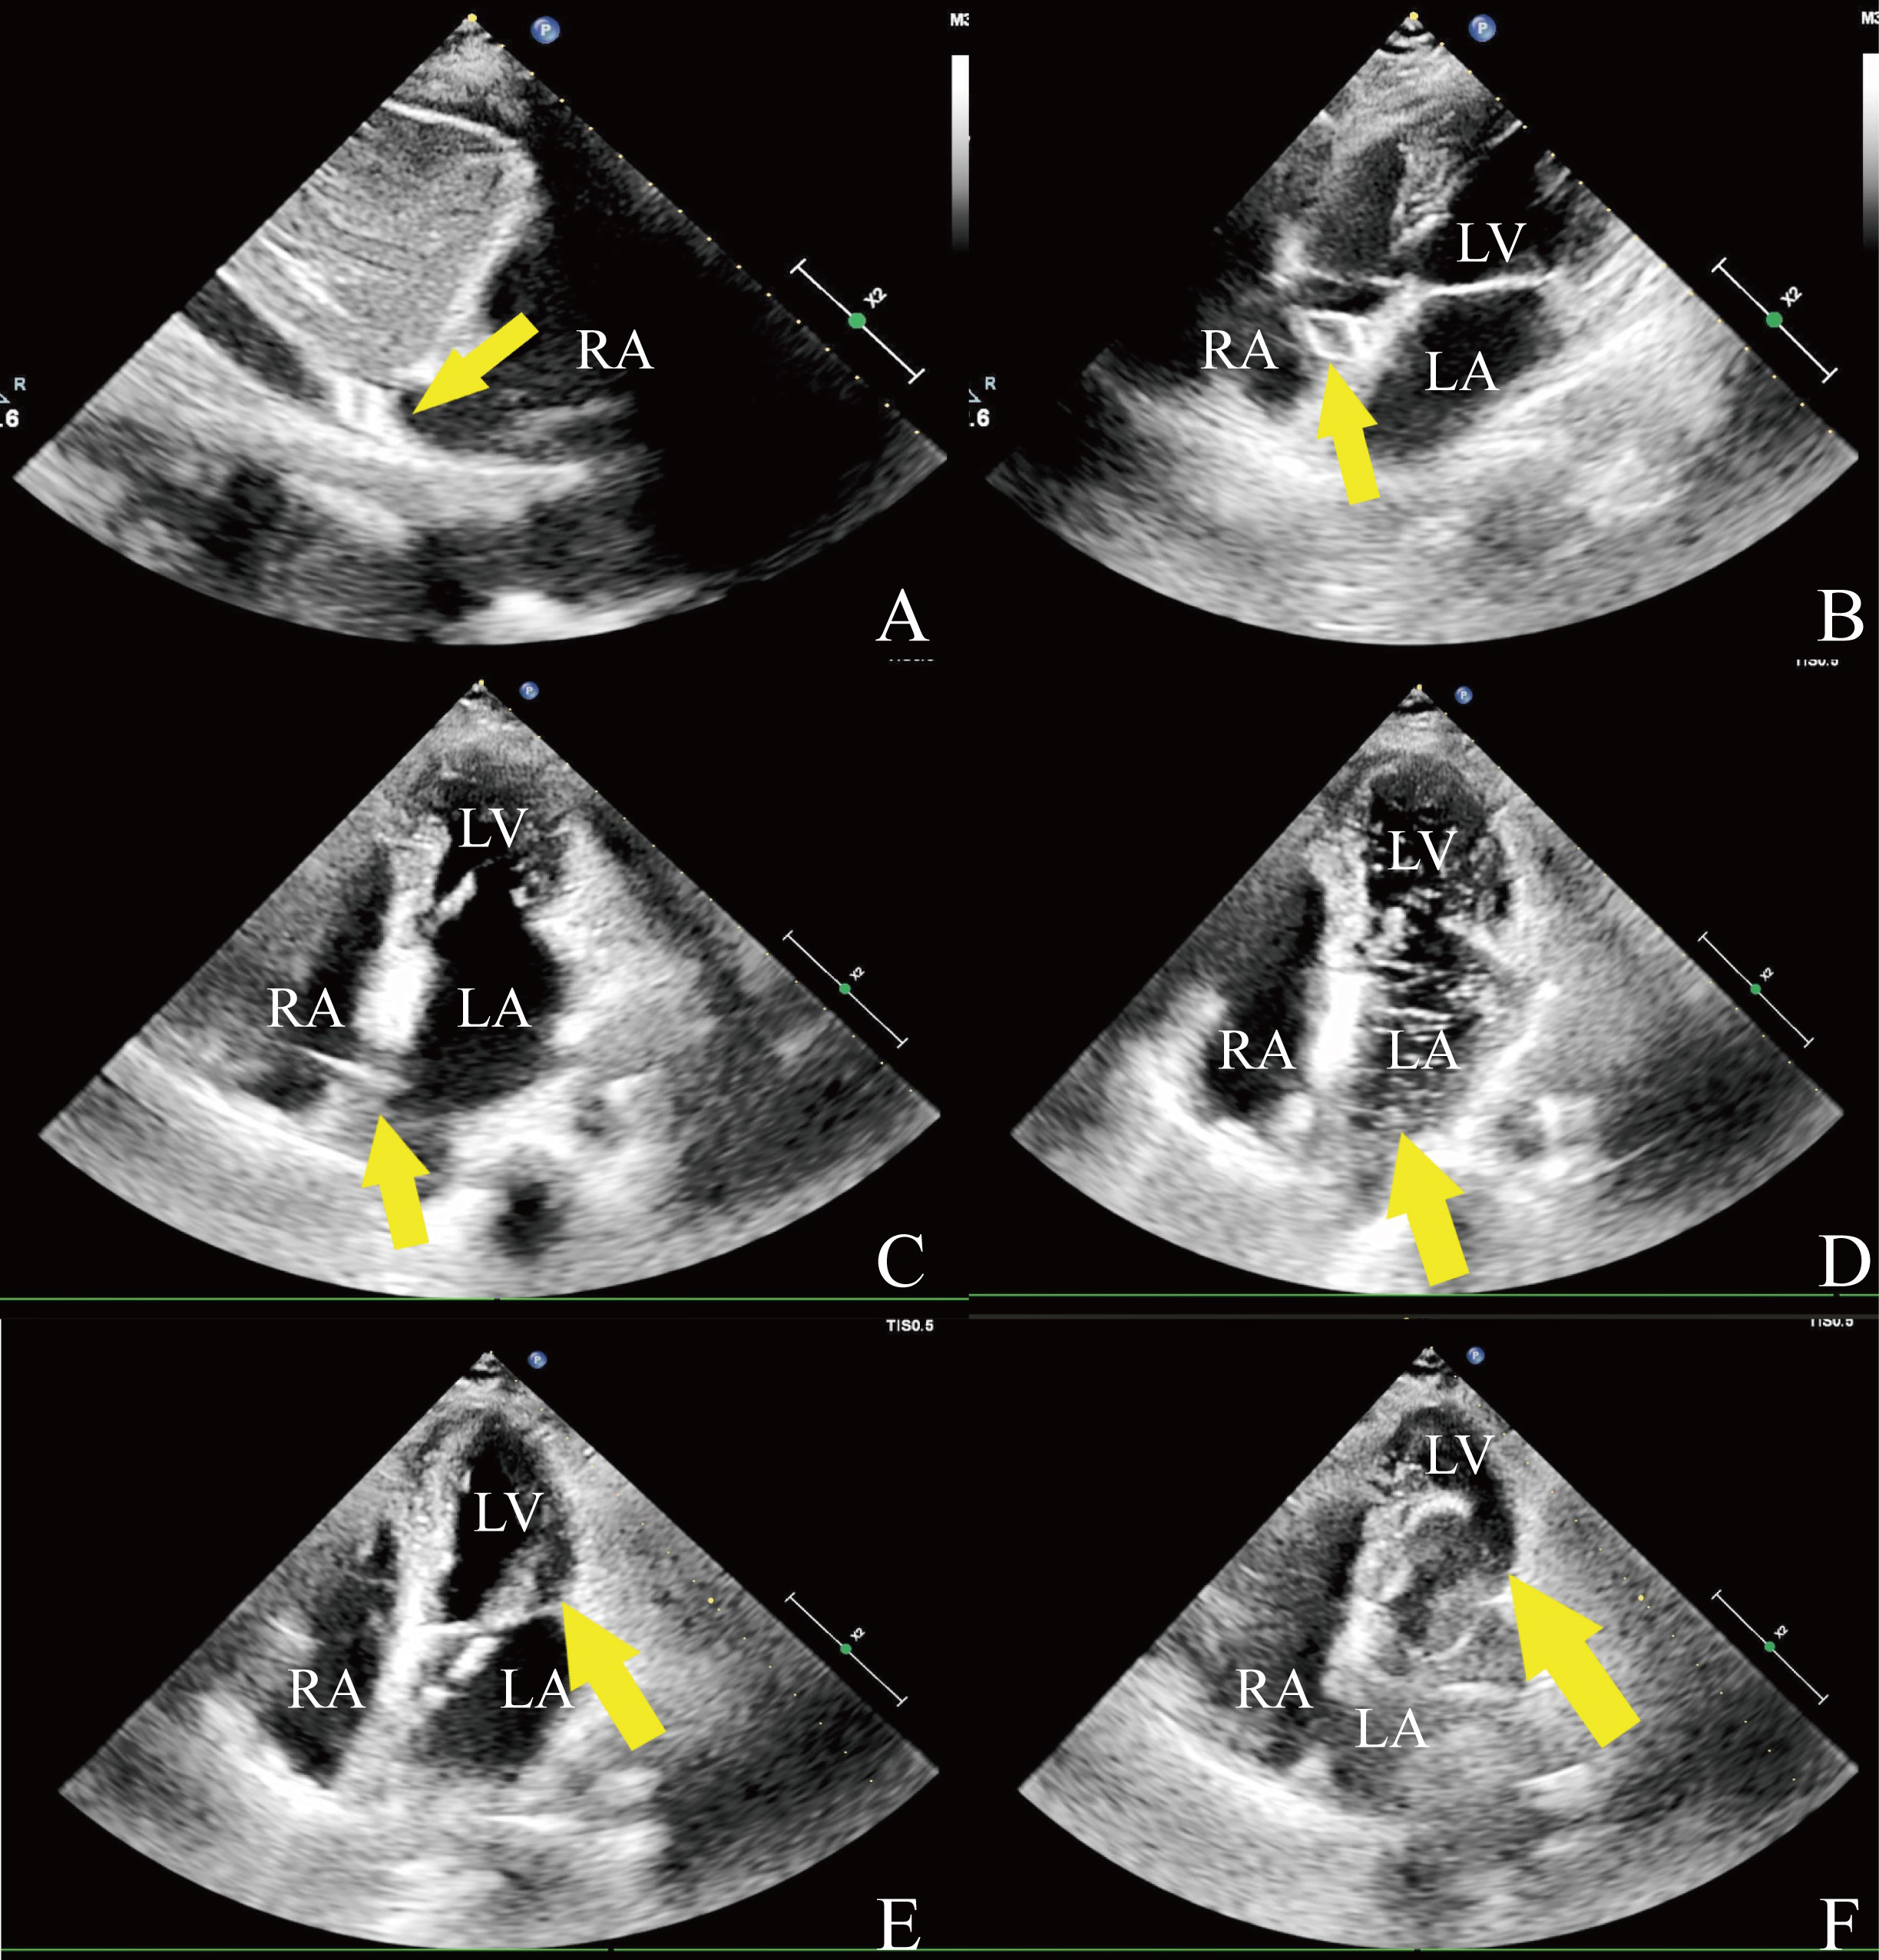

Echocardiography-guided PBMV was conducted by physicians in either general or hybrid operating rooms. Transthoracic echocardiography (TTE) was utilized to reassess the status of MS and to provide imaging guidance throughout the procedure. When TTE imaging was suboptimal, transesophageal echocardiography (TEE) was implemented, noting that TEE necessitates sedation or general anesthesia. The procedure commenced with local anesthesia, followed by puncture of the right femoral vein. Guided by echocardiography, a transseptal puncture sheath and needle were steered along a guidewire. The puncture site was determined by the characteristic tent-like deformation of the interatrial septum visible on echocardiography (Fig. 1C). To verify proper access to the atrial septum, echocardiographic visualization of opacified saline bubbles was performed in the left atrium after the injection of 10 mL of heparinized saline through the sheath (Fig. 1D). An Inoue balloon was then introduced into the left atrium, navigated across the mitral annulus, and into the left ventricle under echocardiographic guidance (Fig. 1E). The balloon was swiftly inflated to dilate the mitral valve once positioned at the valve orifice (Fig. 1F). After achieving full inflation of the balloon waist, the balloon was promptly deflated and carefully retracted back into the left atrium. Echocardiography was employed to assess the effectiveness of the dilation.

Fig. 1. Intraprocedural echocardiography. (A) The wire of the spindle-shaped tip (arrow) in the inferior vena cava. (B) The wire (arrow) is in the right atrium. (C) Tent-like deformation (arrow). (D) Injected saline to confirm access of the catheter tip (arrow) into the left atrium. (E) The catheter passed through (arrow) the stenotic mitral valve. (F) The valvuloplasty balloon (arrow) is inflated across the mitral valve. RA, right atrium; LA, left atrium; LV, left ventricle.

In this study, one patient in the echocardiography-guided group developed mitral valve rupture due to severe leaflet fibrosis, thickening, and adhesion, resulting in chordal rupture at the P2 segment and subsequent severe MR, which required surgical intervention on the third postoperative day. This case underscores the importance of a thorough preoperative assessment, particularly for patients with severe valvular calcification, to minimize the risk of surgical intervention. Echocardiography, which visualizes structures based on their reflective surfaces, may not delineate the catheter and guidewire tip, presenting a significant learning curve due to the differences between echocardiographic and radiation guidance. Therefore, selecting a guidewire detectable by echocardiography is crucial. Indeed, a guidewire with a spindle-shaped tip is more visible under echocardiography [18], facilitating the deployment of the wire and catheter (Fig. 1A,B).